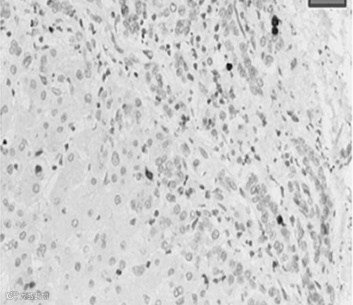

ACLF病理特征可表现为在慢性肝病病理损伤基础上,发生新旧程度不等的肝细胞亚大块坏死性病变,部分患者可伴有汇管周围的小胆管增生。有肝硬化基础的患者,部分硬化结节结构仍然存在。

图1 ACLF病理特征

需要注意的是,由于ACLF患者的肝病基础(非肝硬化/肝硬化)、病因及诱因不同,病理检查提示肝细胞坏死的比例和程度可存在一定的差异。图2左为APASL-ACLF(慢性肝炎和代偿期肝硬化基础)病理特征,在此类人群中,2/3的患者肝脏组织病理学表现为肝细胞坏死和/或肝纤维化,且超过1/3的患者表现为严重肝细胞坏死;图2右为EASL-ACLF(代偿期和失代偿期肝硬化基础)病理特征,在此类人群中,88.5%患者表现为重度肝纤维化,仅37.5%患者出现肝细胞坏死。